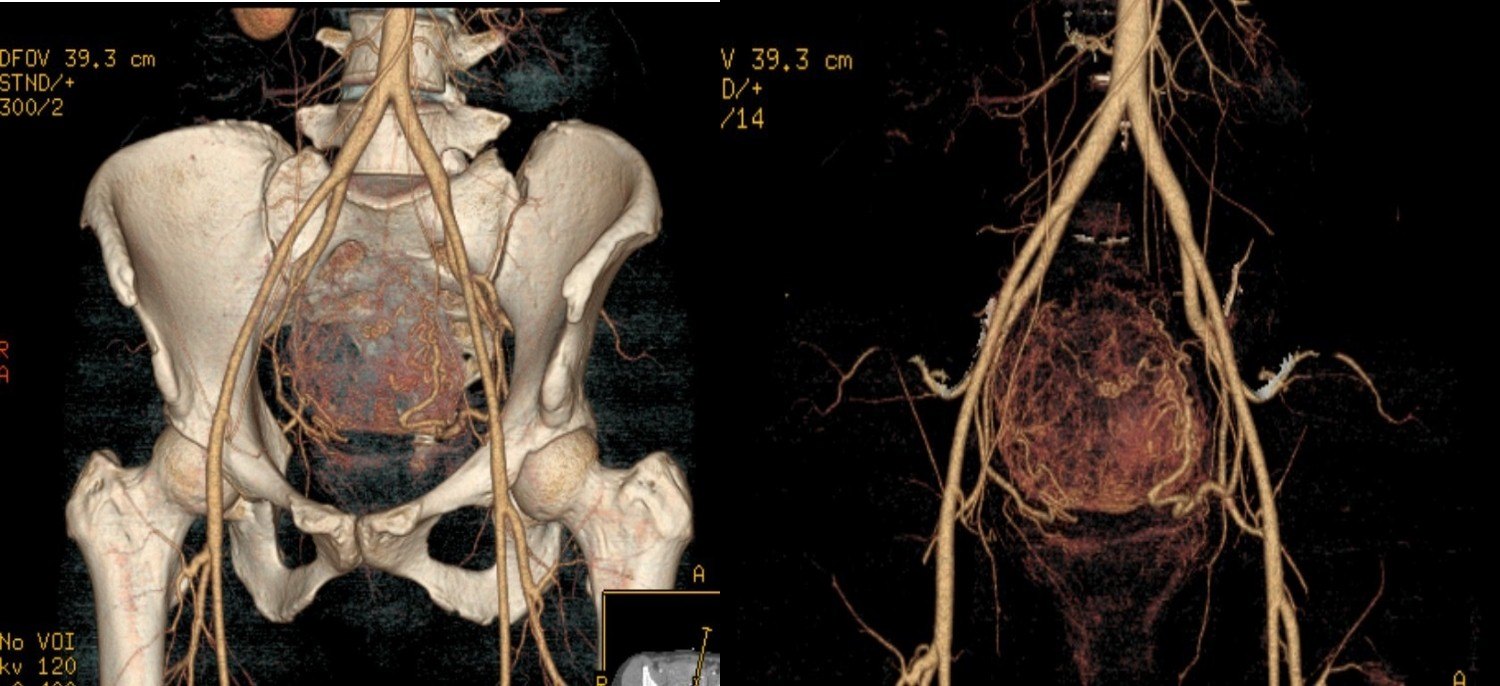

图示:患者术前CTA检查,显示子宫内明显血供增强的肿块-子宫肌瘤